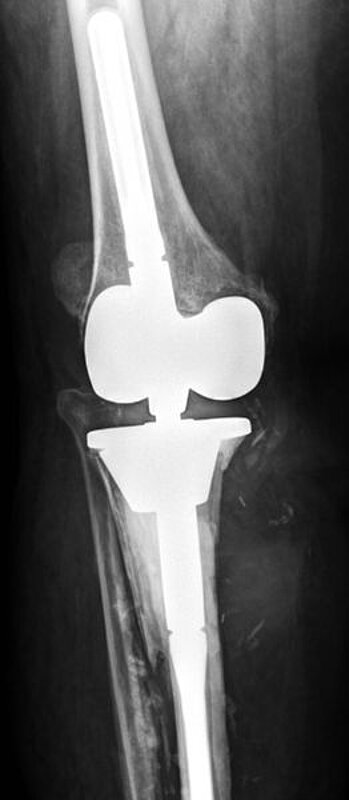

Kurze Vorgeschichte: Herr S, ein 67-jähriger Patient, erhielt 2011 (Abbildung 1) bei ausgeprägter Gonarthrose eine primäre KTEP rechtsseitig. Im weiteren Verlauf zog er sich 2017 eine periprothetische Tibiafraktur zu, die mit einem Knieendoprothesenwechsel auf ein achsgeführtes Implantat (Abbildung 2) und Schaftverlängerung der Tibia im September 2017 ex domo therapiert wurde. Im Verlauf zeigten sich eine anhaltende Sekretion und eine partielle Nekrose am unteren Wundpol.

Eine Röntgendiagnostik des rechten Kniegelenkes in 2 Ebenen wurde eingeleitet. Hierbei zeigte sich eine stabil einsitzende Revisionsprothese ohne aktuelle Lockerungszeichen.

Im weiteren Verlauf zeigten sich die Weichteile des rechten Unterschenkels zunehmend mazeriert und belegt. Zudem sei der Patient erneut gestürzt. Eine erneut durchgeführte Röntgendiagnostik zeigte erneut eine periprothetische Tibiafraktur (Abbildung 3) bei einliegender achsgeführter KTP mit langem tibialem Stem und bekanntem periprothetischem Infekt mit Candida parapsilosis. Wir haben die Befunde ausführlich mit dem Patienten besprochen und in Zusammenschau der Befunde schließlich die Indikation zur Oberschenkelamputation gestellt.